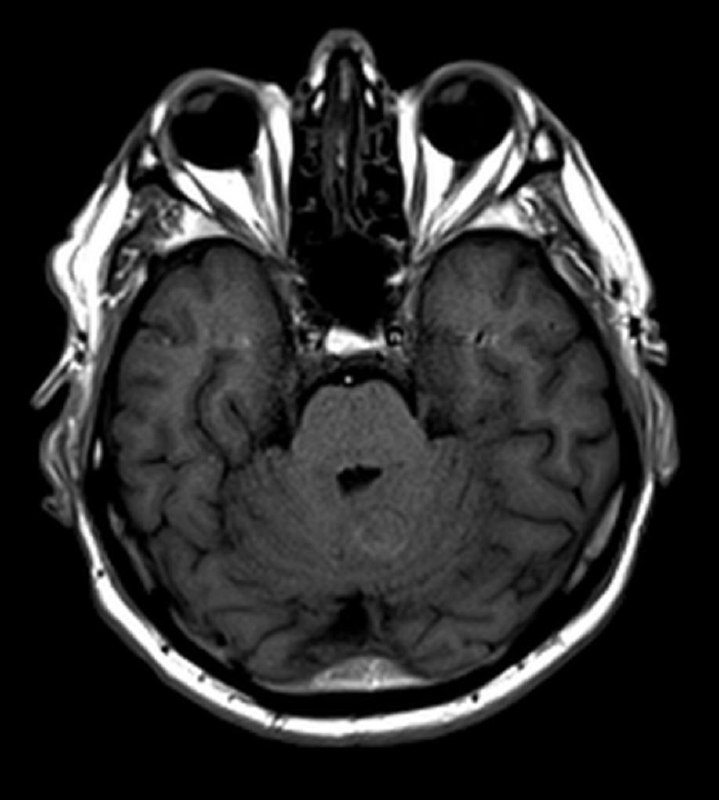

Пациент 35 лет. Жалобы на онемение правой руки. Других жалоб нет.

в декабре 2020 удалена менингиома, а теперь - вот так